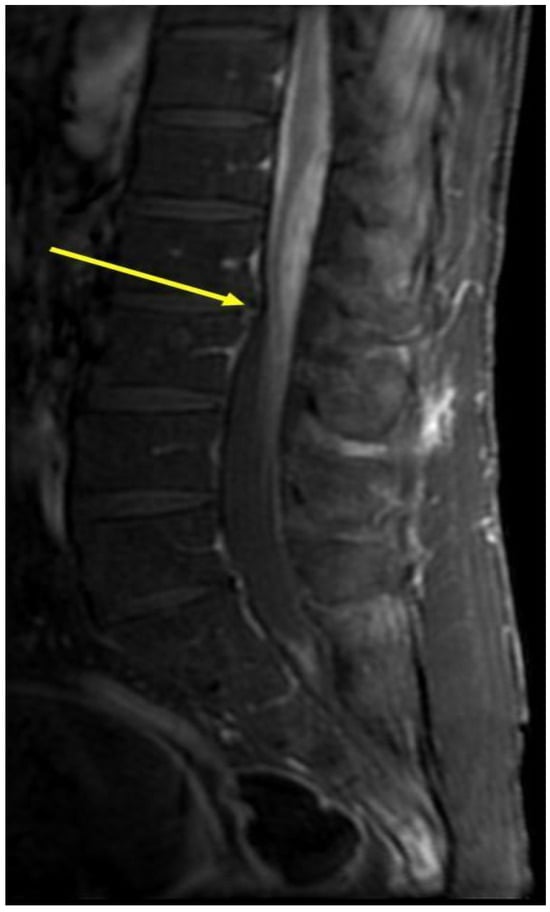

| Lakshman Arcot Jayagopal et al., 2023 [32] | 56/Male | Multi-focal enhancing and longitudinally extensive lesion with dorsal subpial enhancement | Dysesthesia in bilateral arms and legs up to the buttocks and gait difficulties. | Biopsy of a pulmonary mass showed a granuloma | Infliximab: remission of neurosarcoidosis after immunosuppression |